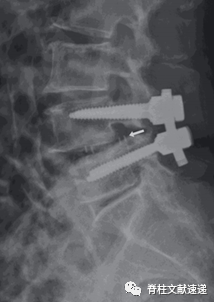

本文为探索cage放置的位置对TLIF术后cage移位有何影响,回顾性分析了953位行TLIF术的患者,用“深度比”评估术后cage矢状位和冠状位的位置(深度比测量方法见下图),用高度差(cage的高度减去术前椎间隙的高度)来评估相对于椎间隙的cage的大小。

通过单变量和多变量分析发现深度比呈负值的患者(OR=9.78E-4;95%CI,9.69E-4-9.87E-4;p<0.001)和高度差呈负值的患者(OR=0.757,95%CI,0.575-0997,p=0.048)术后cage移位的风险明显更高。

文章得出结论,cage放置位置靠后和选择尺寸过小的cage是造成TLIF术后发生cage移位的两个主要危险因素。因此,我们应将cage放置在相对靠前的位置,并且选择高度不小于术前椎间隙高度的cage。

图注:首先确定cage中心点(图a:三角形表示肾形cage的中心点(首先从cage定位点绘制一条与cage定位线平行的线(图a)。cage中心点位于所画平行线和两条cage定位线的几何中心之间的中点)图b:三角形表示子弹形cage的中心点(cage中心点即为两条cage定位线的几何中心点))

图注:如图a所示深度比在侧位X线片上测量cage中心点与椎间盘中心(头端和尾端椎板中点之间的连线)之间的距离除以尾端椎板长度。cage放置位置靠前时,该值定义为正数,cage放置位置靠后时,该值定为负数;